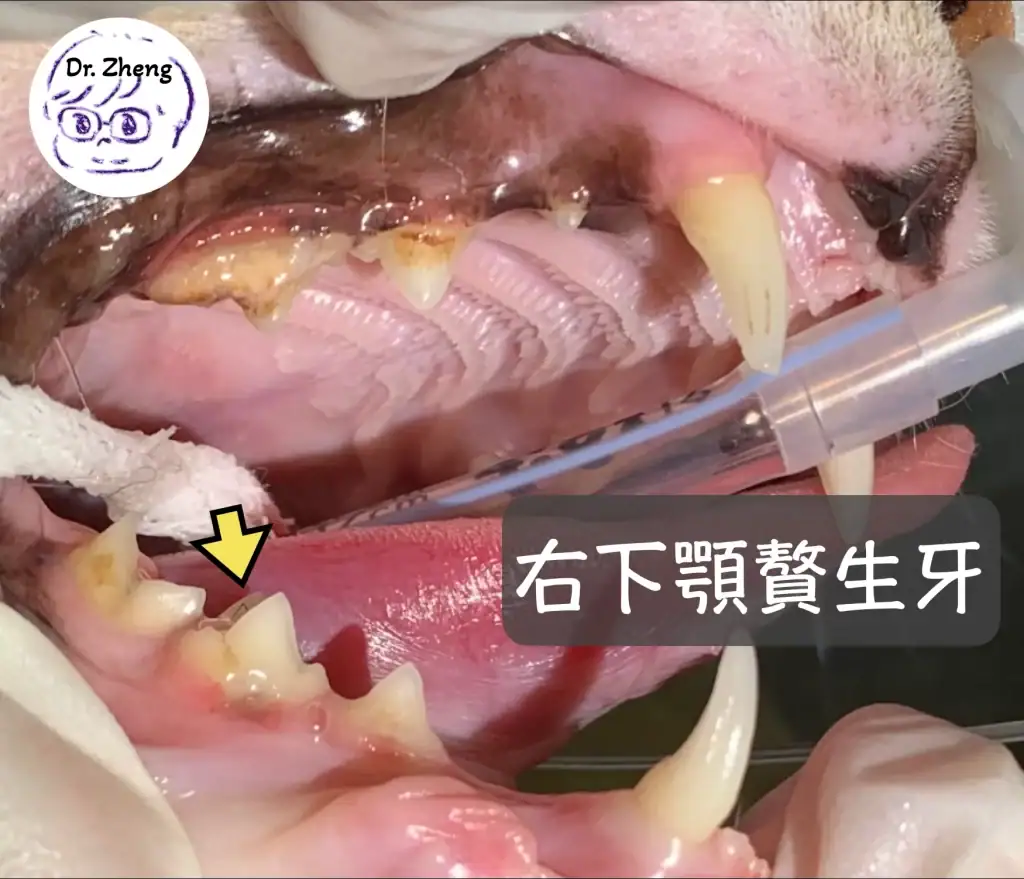

門診檢查紀錄:發現貓咪贅生牙!(Supernumerary teeth)

但再更仔細察看,竟然兩邊下顎都多一顆牙!(見下圖)

*正常下顎後排牙齒只會有3顆,而虎斑卻有4顆牙!這多餘的牙齒也可以稱作多生牙!這是發育上的異常!